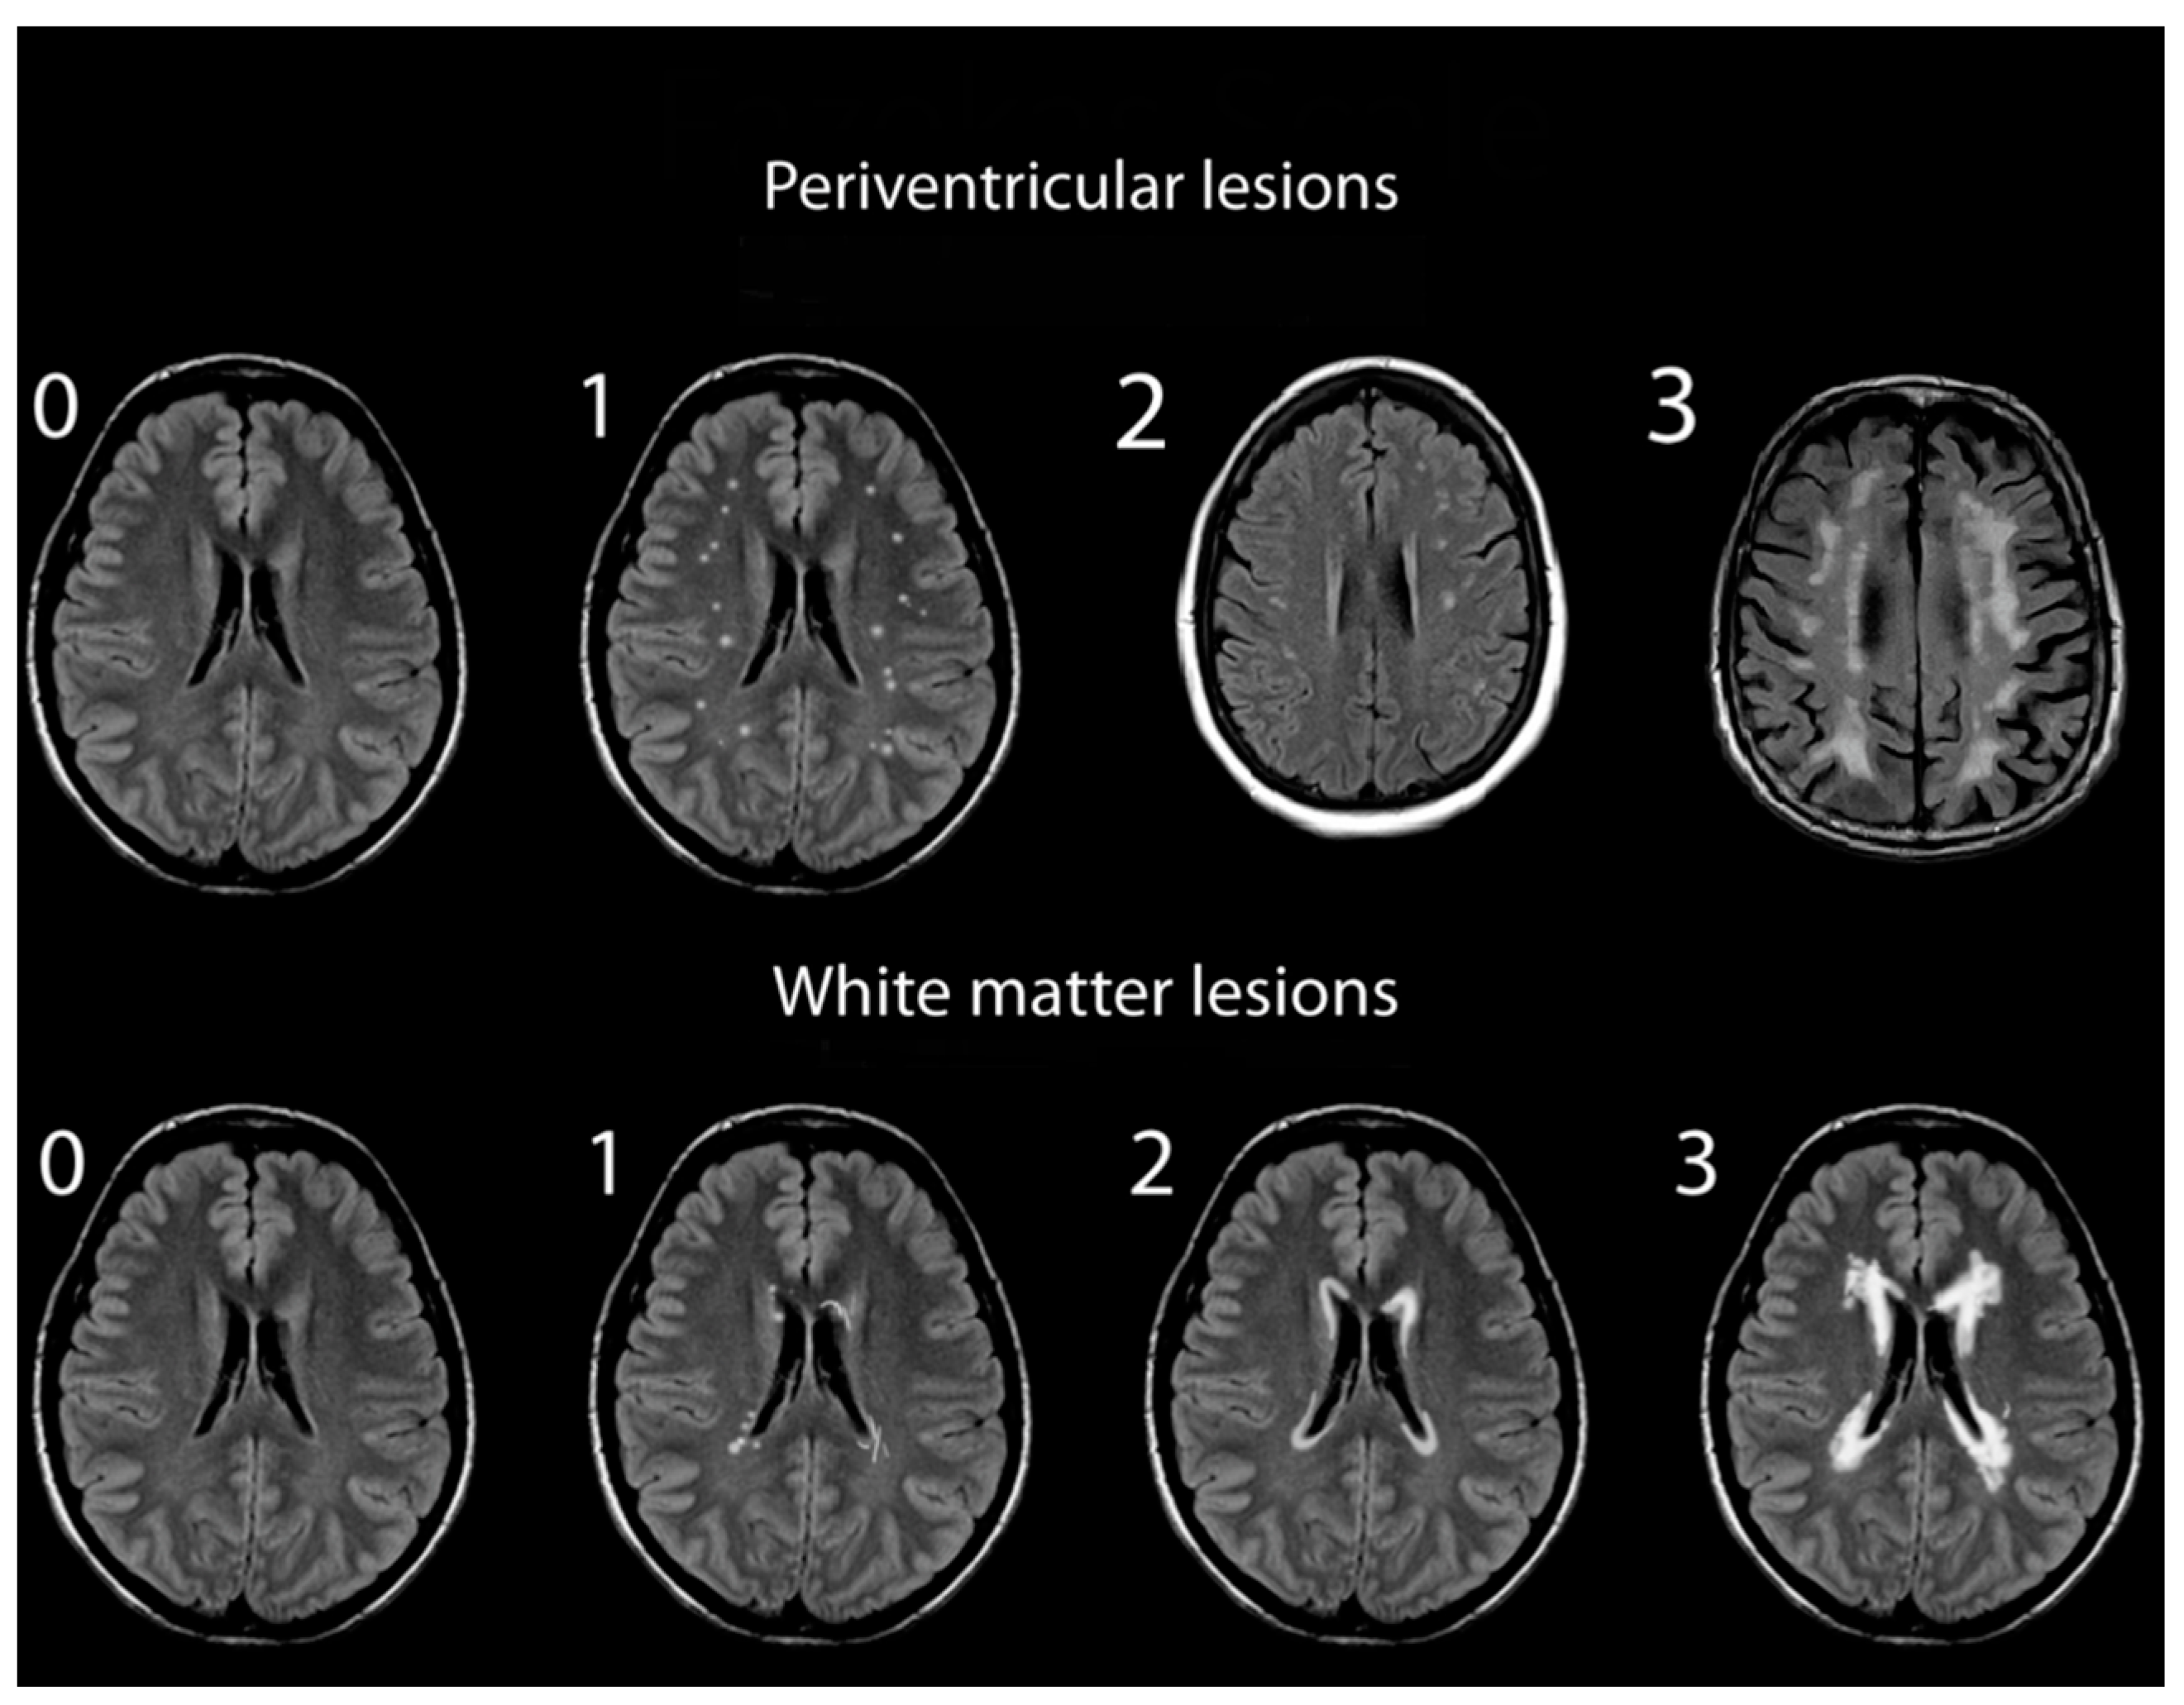

2.2. Assessment of White Matter Hyperintensities

- Mäntylä, R.; Erkinjuntti, T.; Salonen, O.; Aronen, H.J.; Peltonen, T.; Pohjasvaara, T.; Standertskjöld-Nordenstam, C.G. Variable agreement between visual rating scales for white matter hyperintensities on MRI. Comparison of 13 rating scales in a poststroke cohort. Stroke 1997, 28, 1614–1623. [Google Scholar] [CrossRef]

- Mirsen, T.R.; Lee, D.H.; Wong, C.J.; Diaz, J.F.; Fox, A.J.; Hachinski, V.C.; Merskey, H. Clinical correlates of white-matter changes on magnetic resonance imaging scans of the brain. Arch. Neurol. 1991, 48, 1015–1021. [Google Scholar] [CrossRef]